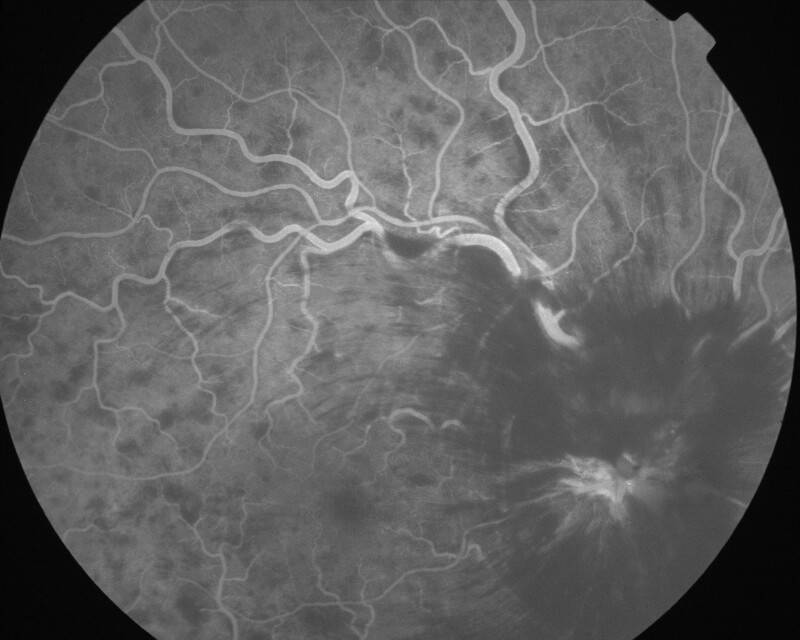

IMG0019.jpg